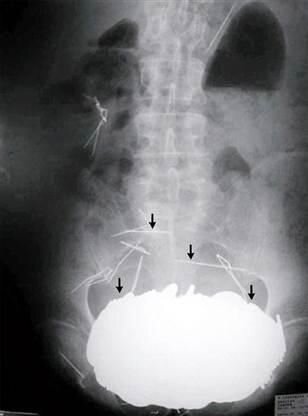

Практически всю "вырученную" сумму мужчина в итоге потратил на операцию по освобождению своих внутренностей от сокровища - в животе скопилось почти 5,5 кг денег, которые начали причинять сильные боли, желудок перестал переваривать твердую пищу, а живот стал визуально заметно провисать, практически мячом для боулинга ниже бедер. Профессиональные медицинские журналы даже публиковали рентген:

Возможно, что-то из съеденного клада и переварилось, но основная сумма наверняка выжила - врачам пришлось делать не одну операцию и буквально по монетке облегчать "копилку".

Кстати, помимо франков и евро, доктора извлекли и пару-тройку ювелирных украшений.